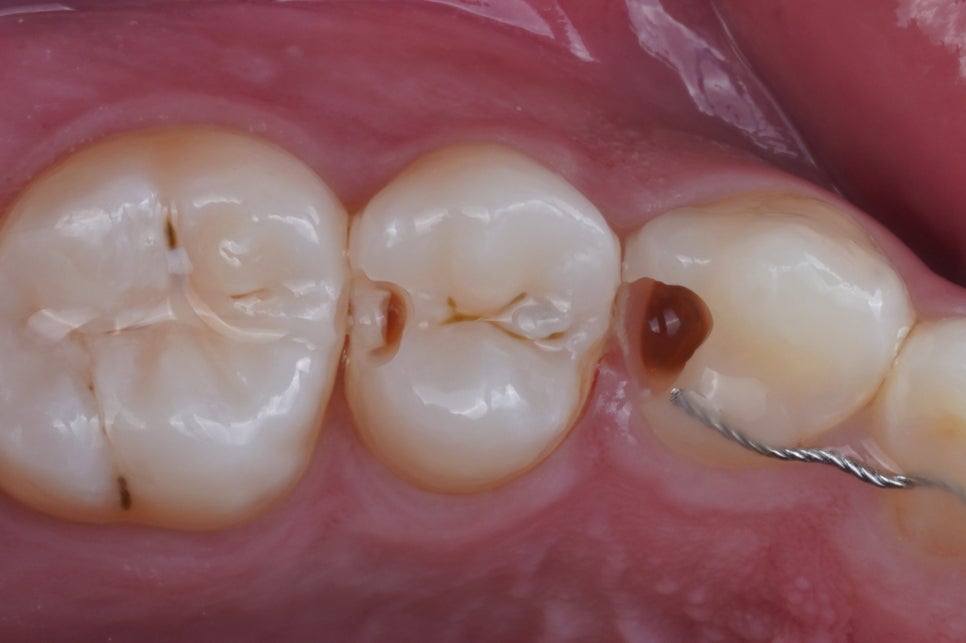

그리고 이렇게 하기 위해서는

러버댐이라는 재료를 잘 써야 해요.

러버댐을 잘 쓰는 것이

가장 중요한 첫단계입니다.

러버댐이라는 재료는

그냥 썼다고해서 다 된 게 아니라

그 목적을 이루기 위해 필요한 여러 원칙들을

하나하나 지켜야만

원하는 결과를 얻을 수 있겠죠.

어금니, 앞니 가릴 것 없이

중요한 접착의 순간에

이렇게 러버댐을 사용하는 것,

그래서 구강 내에 있는

뺨과 혀,

피와 침과 습기로부터

치아를 완전히 격리하고 방습하는 것.

그것이 교과서에 적힌 원칙이고

결과를 High-end로 유지할 수 있는

비결입니다.